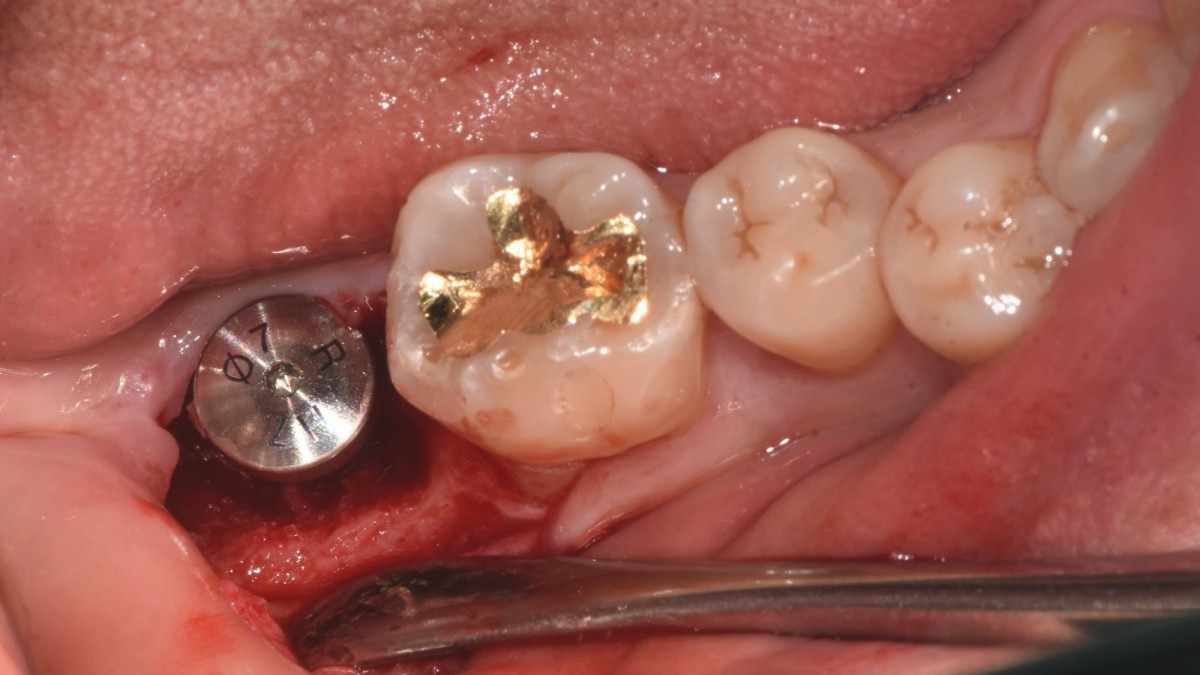

Single implant (staged) Arum NB1, f/u

A 47-year-old male patient had a crown with an ill-fitting margin and crack-tooth syndrome in the lower 2nd molar. No systemic issue.